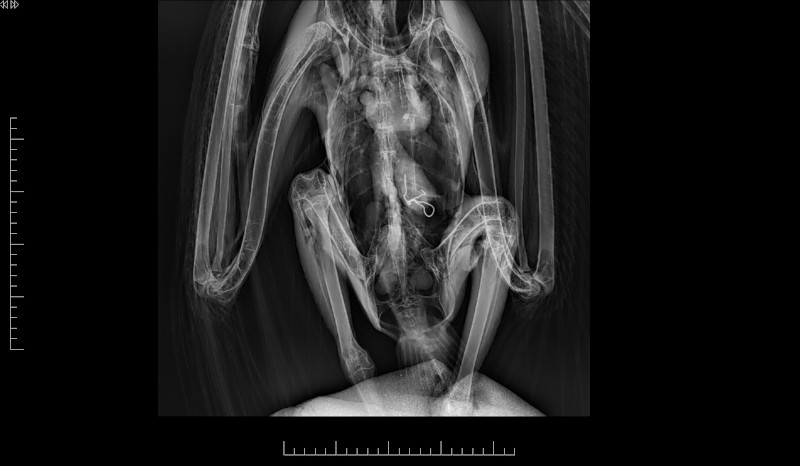

Agentes Forestales de la Comunidad de Madrid rescataron el pasado 2 de septiembre a un buitre leonado que accidentalmente fue a parar al patio de la cárcel de Estremera. El ave fue trasladada al Hospital de Fauna Salvaje de GREFA, donde se le diagnosticó una intoxicación por plomo, deshidratación, hipotermia y bradicardia, además de detectarle un alambre de unos siete centímetros en su aparato digestivo.

El equipo veterinario de GREFA tuvo que intervenir quirúrgicamente de urgencia al buitre leonado rescatado para extraer el alambre, una operación que resultó todo un éxito. Actualmente, el buitre se encuentra en proceso de recuperación en las instalaciones de nuestra ONG conservacionista destinadas a este fin, aunque su evolución dependerá también de cómo responda al tratamiento contra la intoxicación por plomo.

El buitre leonado rescatado tras la operación y anestesiado en el quirófano de GREFA.